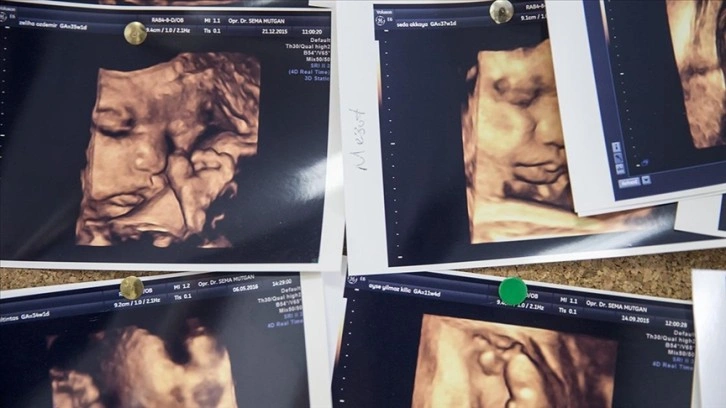

Anne karnındaki bebek sayısının iki veya daha fazla olması durumuna çoğul gebelik deniliyor.

Türkiye İstatistik Kurumunun (TÜİK) verilerine göre, 2019'da doğumların yüzde 3,1'i çoğul doğum olurken, bu doğumların yüzde 96,4'ünün ikiz, yüzde 3,4'ünün üçüz ve yüzde 0,2'si dördüz ve daha fazla bebek oldu.

2019'da yüzde 3,1 olan çoğul doğum oranı 2020'de yüzde 2,9'a gerilerken, 2021'de tekrar yüzde 3,1'e yükseldi.

2022'deki 1 milyon 35 bin 795 doğumun yüzde 3,2'si çoğul doğum oldu.